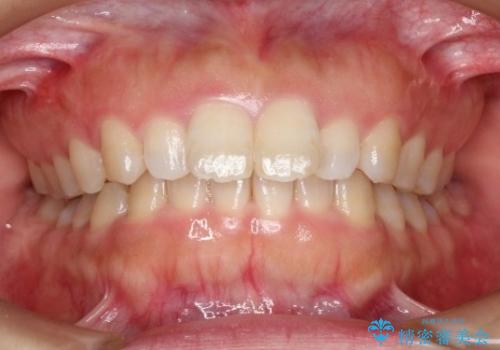

八重歯をインビザラインで非抜歯矯正